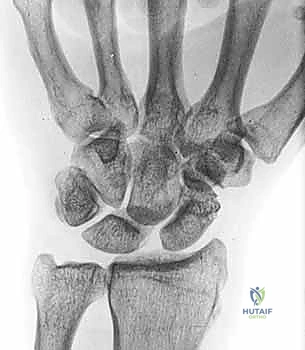

Radiographs, while not always definitive in early stages, provide crucial information.

* PA View: We look for a scapholunate gap >3mm or wider than the contralateral side, and the cortical "ring" sign.

* AP View (Clenched-fist): This view accentuates the scapholunate gap by applying axial load.

FIG 2 • A. Clenched-fist PA view with the wrist in supination, demonstrating a significant increase in the scapholunate interval space.